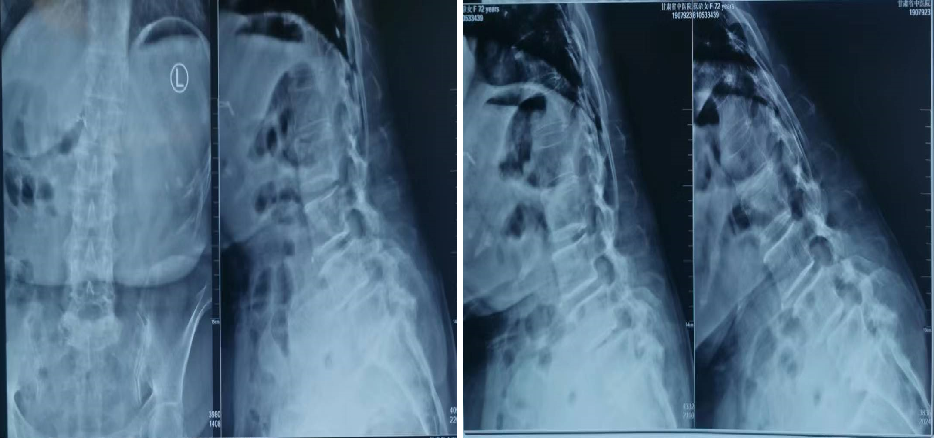

腰椎滑脱Meyerding分级